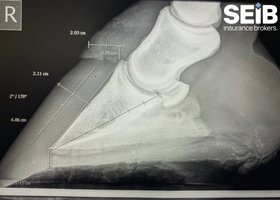

- The endocrine factors behind laminitis, including PPID and EMS

- Factors that predispose horses to laminitis

- Diagnosis, management, and guidance for owners dealing with PPID and EMS